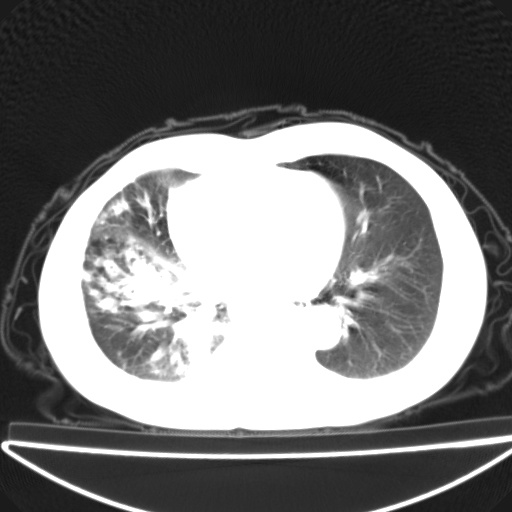

以下是引用jsgdoctor在2008-11-6 22:12:00的发言:[br]右主支气管壁明显增厚,管腔狭窄.考虑为右侧中央型肺癌伴阻塞性炎症\\肺脓肿.

以下是引用zjzjr在2008-11-6 20:25:00的发言:[br]中心型肺ca,合并阻塞性肺炎

以下是引用zsl6918在2008-11-6 19:43:00的发言:[br]右侧中心性肺癌(鳞癌)